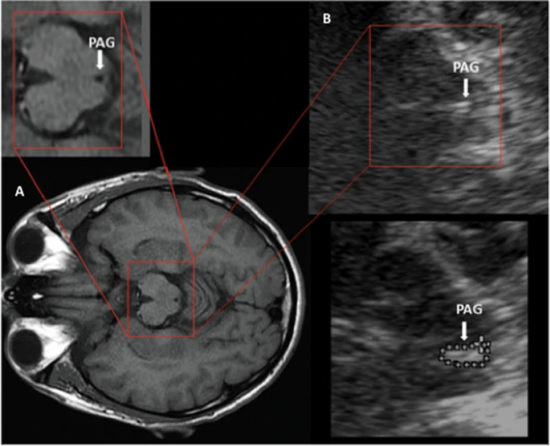

Deep Brain Reorienting (DBR) es una intervención terapéutica que actúa directamente sobre las respuestas neurofisiológicas automáticas asociadas a situaciones de amenaza, con especial énfasis en los mecanismos regulados por el tronco encefálico, estructura encargada de las respuestas instintivas de supervivencia.

El abordaje terapéutico se centra en identificar y procesar el shock preafectivo (la activación neurobiológica que ocurre antes de que la experiencia se manifieste a nivel consciente, emocional o cognitivo), permitiendo así la descarga adaptativa de patrones de respuesta que suelen estar generalizados en múltiples áreas de la vida del paciente.